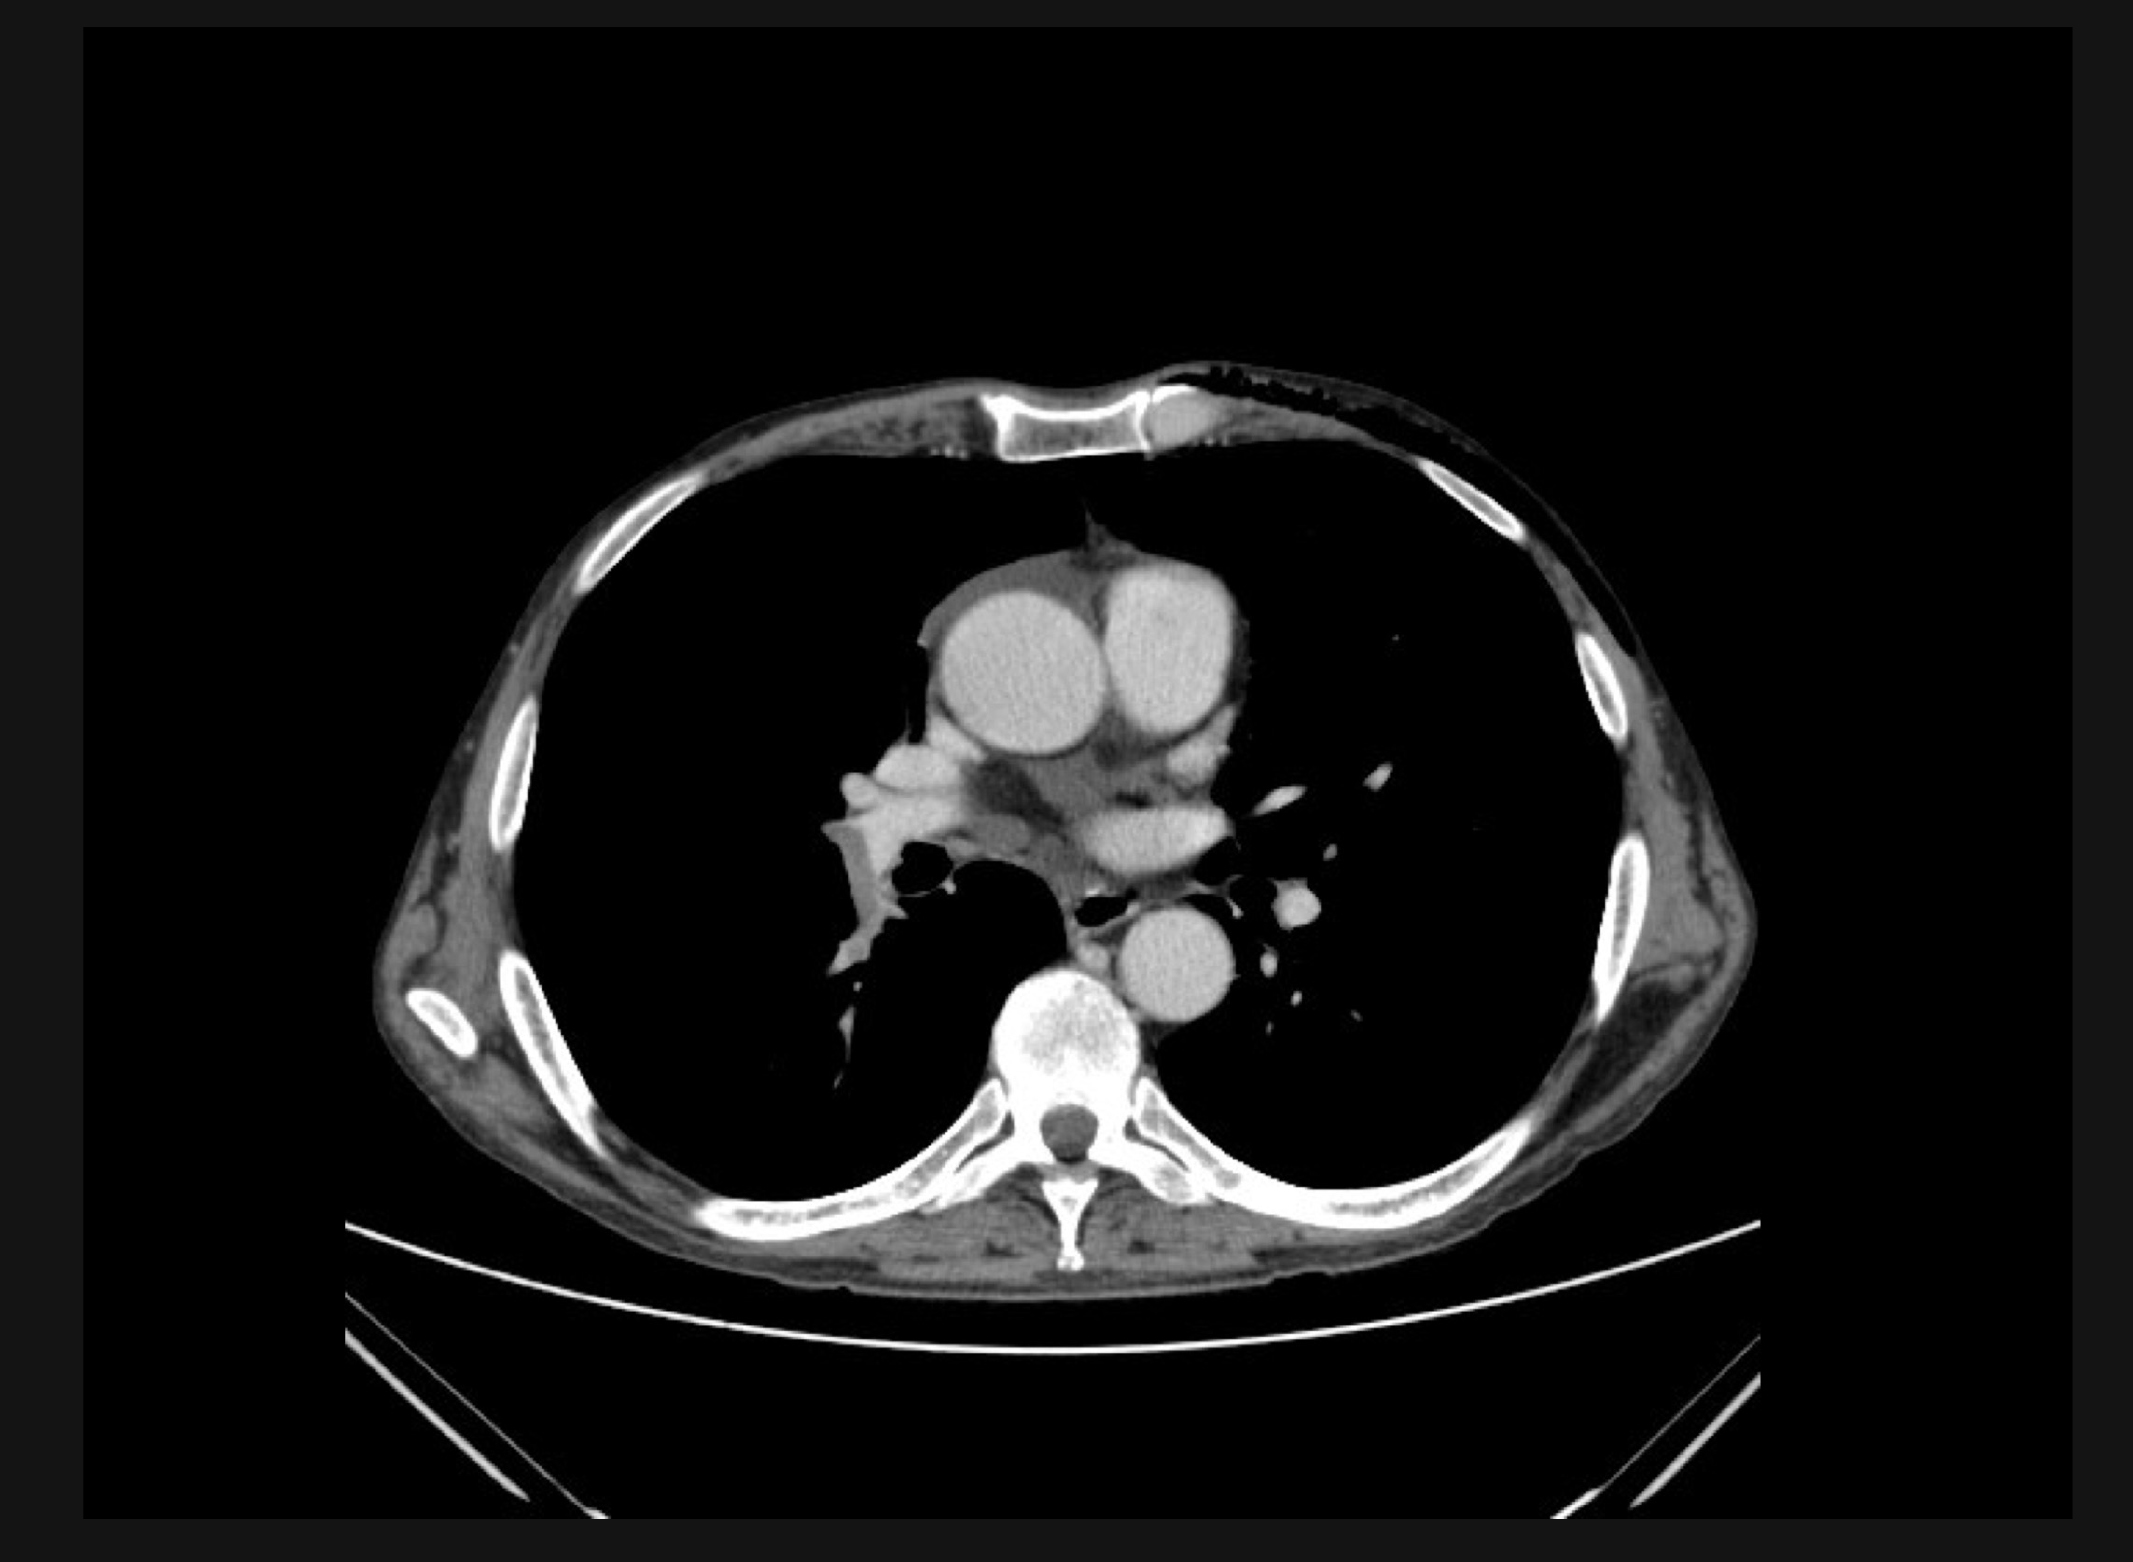

El paciente acudió a urgencias por cefalea hemicraneal persistente que no cedía con analgésicos. A la exploración neurológica se le halló obnubilado sin clara focalidad neurológica por lo que se solicitó un TC craneal que mostró dos imágenes sugestivas de metástasis (Figura 1), con edema perilesional y efecto masa. Se realizó un TC torácico por imagen sugestiva de neoplasia en radiología simple, que mostró una lesión en parénquima pulmonar de 33x26 mm de bordes irregulares y contornos espiculados, situada en el segmento apical posterior del lóbulo superior izquierdo, la cual contacta la cisura. Imagen muy sugestiva de neoplasia primaria de pulmón (Figura 2).